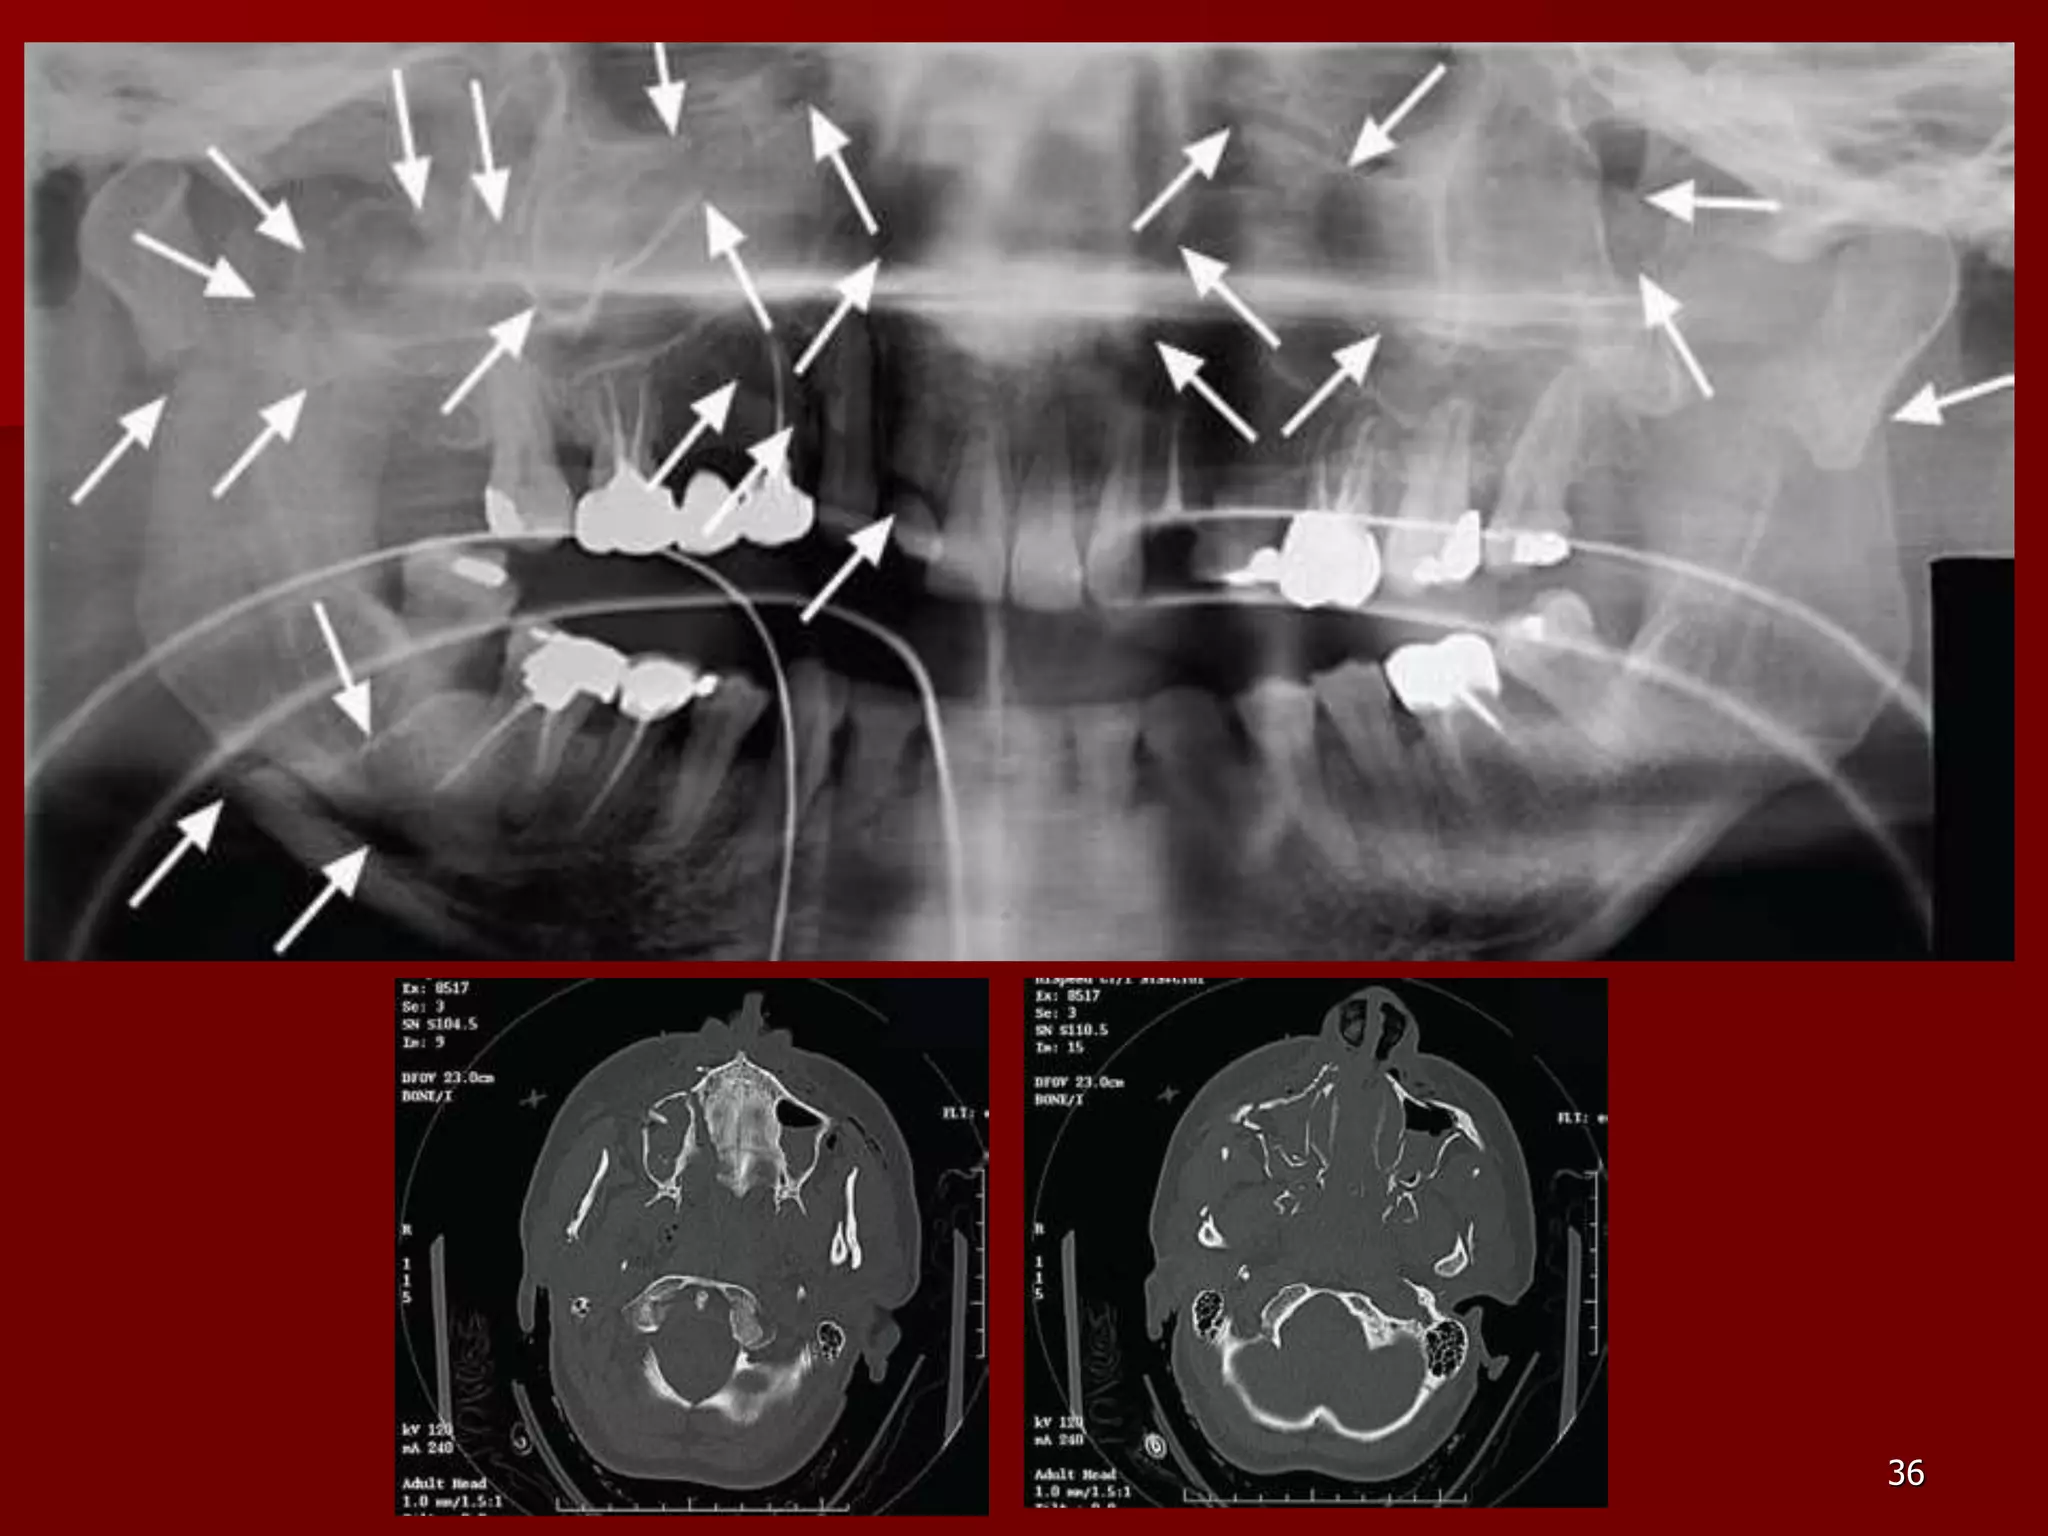

 Fractura apofizei coronoide – are

simptomatologie discreta, linia de fractura este

unica si deplasarea este redusa.

 Fracturi multiple ale mandibulei – la un

traumatism complex se pot produce fracturi cu

trei traiecte, simfizar si doua traiecte la nivelul

corpului mandibular sau la nivelul gonioanelor.